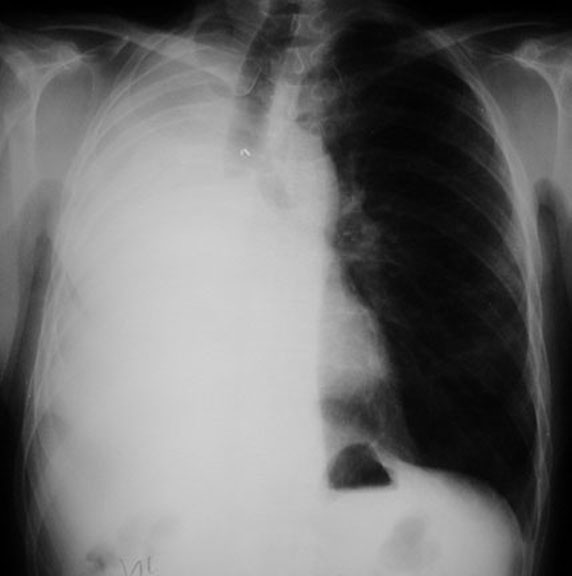

Which lung is resected?

• Note that you can see only one diaphragm in the film on the left. The film below  is pre-pneumonectomy, where you can identify both diaphragms.

• The visible diaphragm has a stomach bubble underneath, indicating that it is on the left.

• Hence, right lung pneumonectomy has occurred.